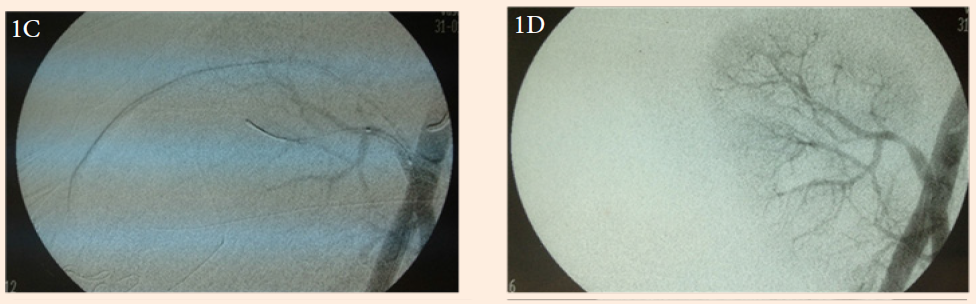

A 46-year old woman underwent living donor kidney transplantation on 01/30/2012. The donor was her sister and the donated kidney had an inferior polar artery that was anastomosed to the main renal artery. The recipient showed good diuresis during the early hours, followed by an abrupt decrease of urine output. An ultrasound (US) revealed a renal-iliac resistance index and intrarenal resistance index of 1.34 and 0.5, respectively. However, intrarenal pulsatility determined by US Doppler showed a parvus et tardus pulse pattern suggesting thrombosis of the intrarenal arteries or renal artery stenosis. A diagnostic arteriography indicated less than 24 hours postoperatively revealed a full anastomosis contrast without stenosis, but a faint contrast filling of the intrarenal arteries (Figure 1A). These arteries were selectively catheterized and 15 mg of recombinant tissue plasminogen activator (rTPA) was injected for intrarenal thrombolysis (Figure 1B). There was some improvement in the intrarenal filling pattern, but there was also an area of spasm (stenosis) of the renal artery 1 cm from the anastomosis. Balloon angioplasty was performed, followed by an intra luminal post anastomotic renal artery stent (Figure 1C). An immediate control arteriography showed excellent perfusion (Figure 1D). Serum creatinine was reduced from 6.3 to 1.22 mg/dL within five days and remained at 1.16 mg/dL during the late postoperative period (Figure 2). The patient continues to have normal renal function and normal US Doppler. The only complication was an 11.3 by 5.2 cm graft site hematoma treated with percutaneous drainage using a Jackson-Pratt (Blake) drain.

Figure 1a Initial arteriography showing impaired postanastomotic perfusion.

Figure 1B Selective renal artery thrombolysis with 15 mg rTPA.

Figure 1C Renal artery spasm (stenosis) before stenting.

Figure 1D Final arteriography showing normal renal transplant perfusion.